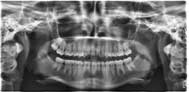

Un

cliché Panoramique Dentaire qui permet |

| d’apprécier la position et l’état des dents |

| d’apprécier la structure osseuse |

| d’apprécier l’état des articulations de la mâchoire |